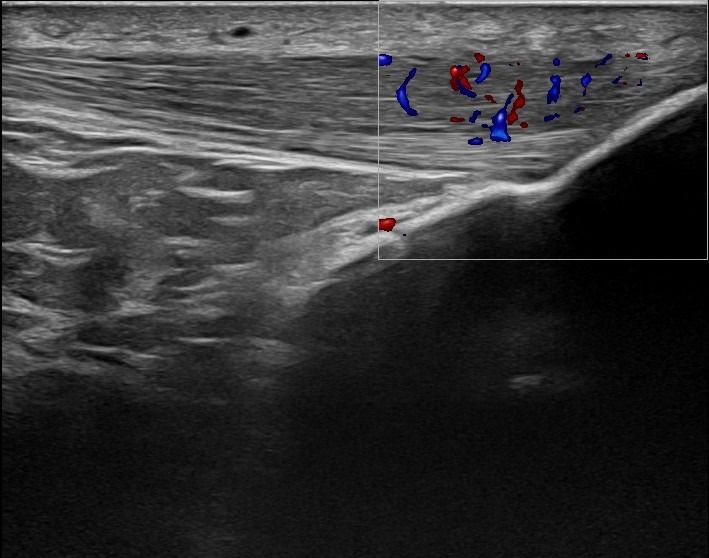

Το Υπερηχογράφημα Γόνατος προσφέρει τη δυνατότητα απεικόνισης παθολογιών στην άρθρωση, τους θυλάκους, τους τένοντες, τους συνδέσμους, τα νεύρα, τα αγγεία και τα μαλακά μόρια της περιοχής του γόνατος.

Η παρουσία συλλογής υγρού, θυλακίτιδας ή υμενίτιδας που ανιχνεύεται με το Υπερηχογράφημα Γόνατος μπορεί να σχετίζεται με ρευματολογική νόσο, όπως:

Αγγεία και Νεύρα Γόνατος

- Θρόμβωση στην Ιγνυακή Φλέβα

- Ανεύρυσμα στην Ιγνυακή Αρτηρία